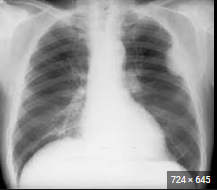

Las figuras 1, 2 y 3 ilustran ejemplos de signo, hallazgo y patrón.

Ejemplo de hallazgo. Se ven dos nódulos pulmonares encontrados de forma casual en. Correspondían a metástasis de un cáncer de colon no conocido.